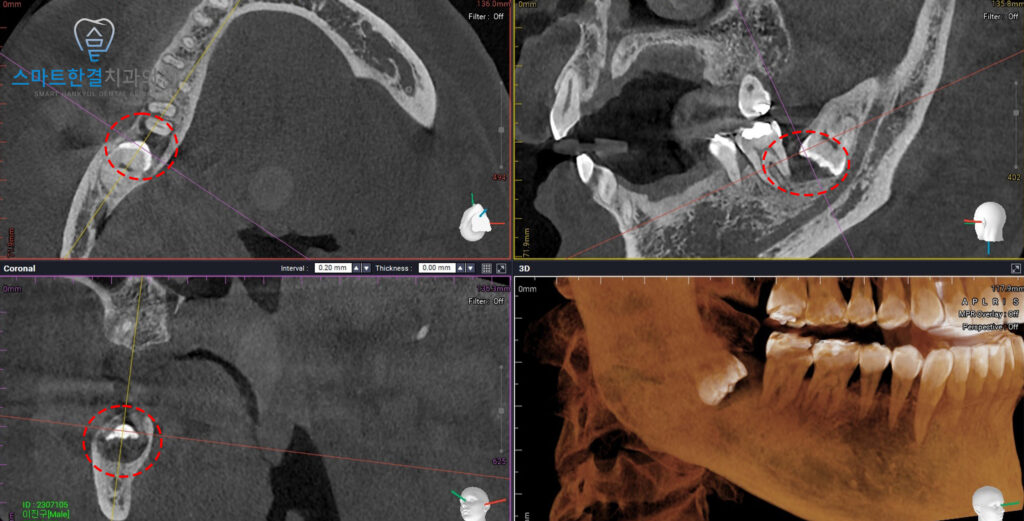

<CT에서도 명확히 보이는 낭종>

정밀한 확인을 위해

CT를 촬영해 보니,

CT 상에서도 낭종이

명확히 보이는 것을 확인할 수 있었어요.

또한 해당 낭종이 매복 사랑니 주변에만

국한된 것이 아니라

앞쪽 인접 치아 부위까지 영향을 줄 수 있는

위치와 크기로 관찰되어 적극적인 치료가

필요한 상태로 판단되었는데요.

이에 화서동치과 스마트한결에서는

함치성 낭종으로 진단하였으며,

더 증가하고 불편함이 커지기 전에

사랑니 발치와 함께 낭종적출술을 진행하기로

계획을 수립하였답니다.